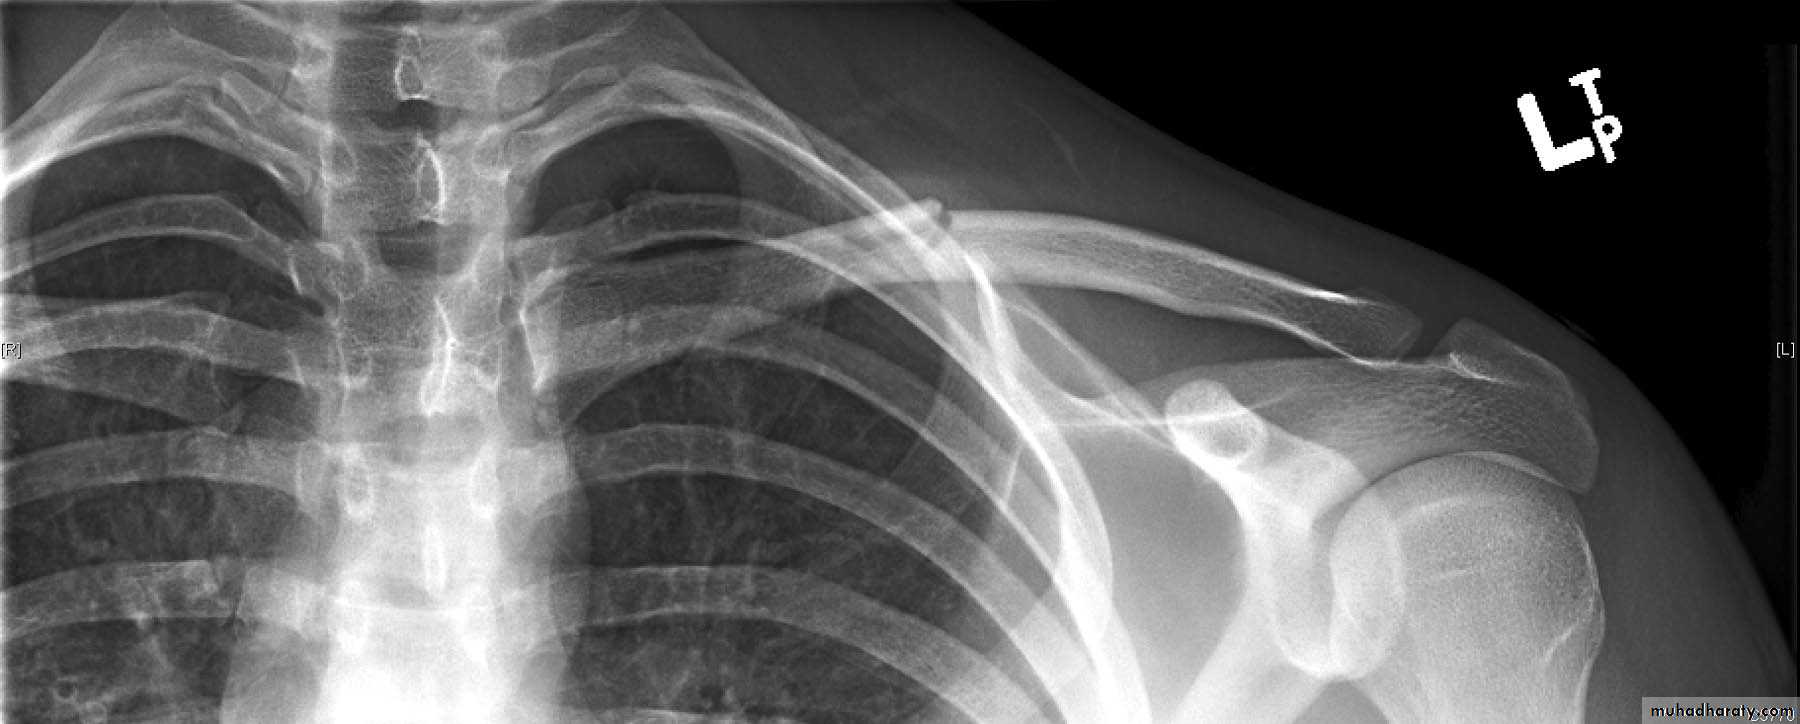

1-Fractue clavicle

2-Fracture scapula